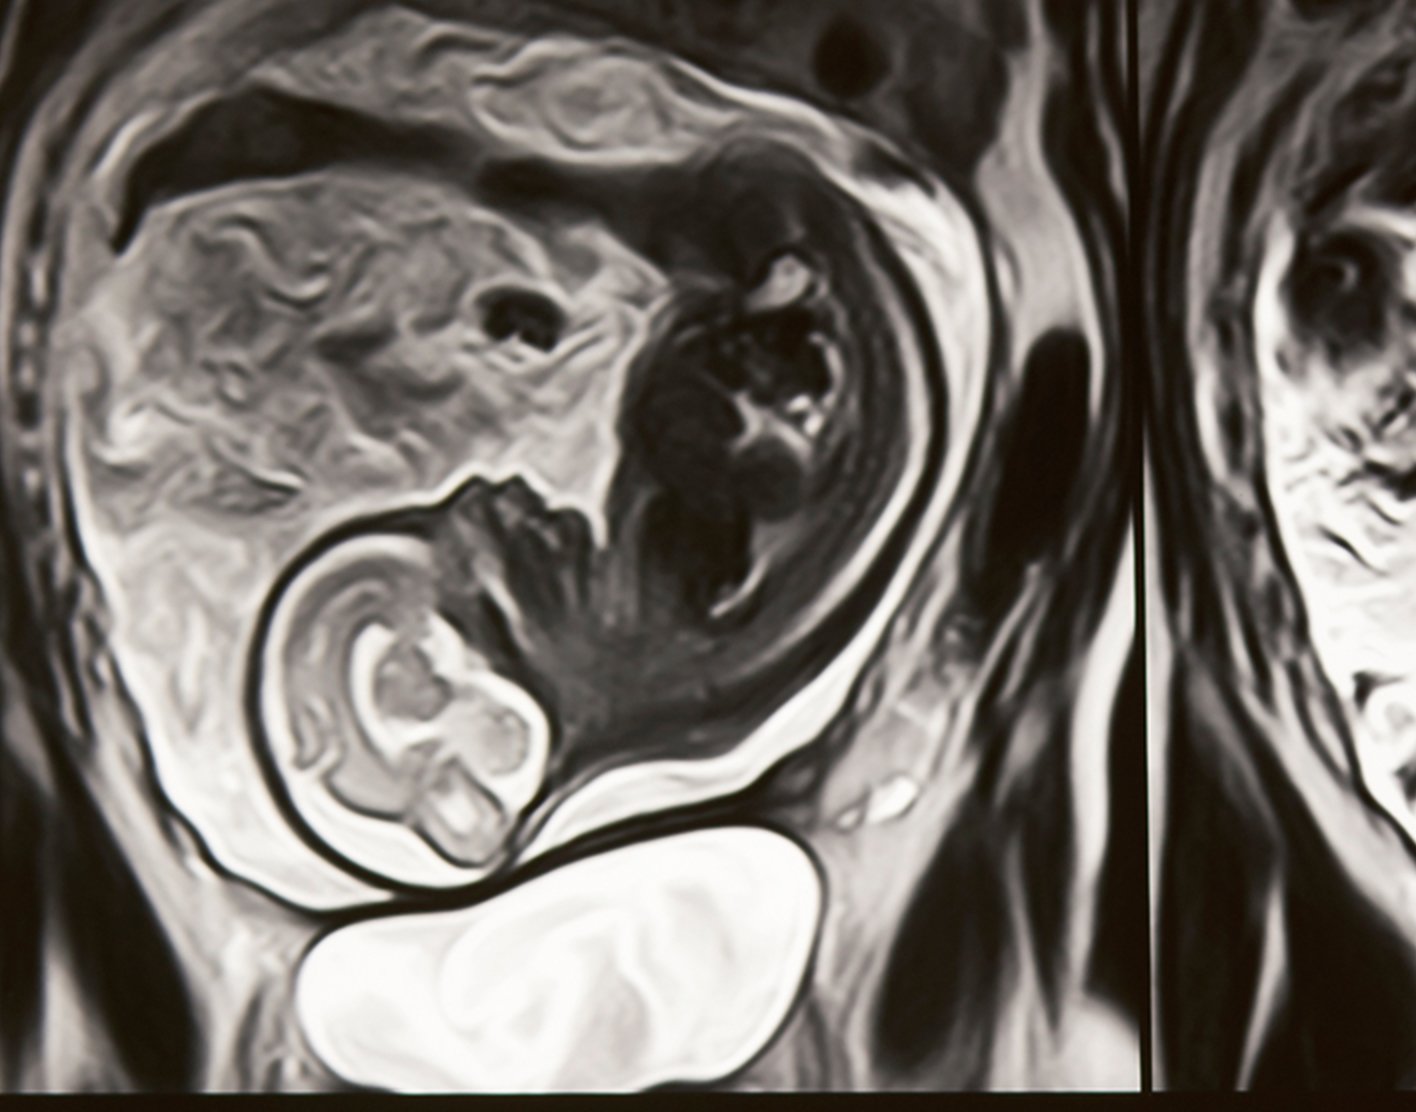

Fetal MRI

Magnetic Resonance Imaging (MRI) is a well-established diagnostic imaging technique that uses a strong magnetic field and radio waves to obtain pictures of the inside of the body without utilizing radiation. The MRI machine acquires data regarding the fetus without causing harm and creates detailed images in different angles that radiologists and other members of the Fetal Medicine team can view. From the published literature, it would appear that MRI provides additional diagnostic information to that given by ultrasound in nearly half of the cases, which in turn may have influence on prenatal counseling and/or management of affected pregnancies.